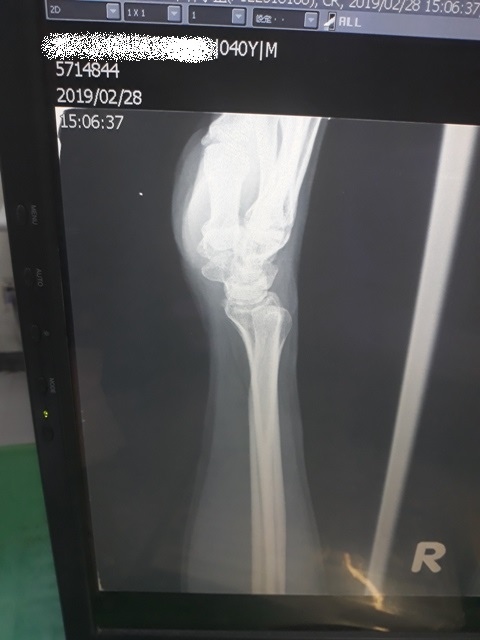

今日所拍的X光照↓

這三次回診的X光片,相較前兩次,今天已經癒合許多了↓

或許今天是228放假日,來醫院看病的人蠻多的,我們等了一段時間才被叫到。進到診間後,黃醫師調出X光資料,發現橈骨已癒合很多了,讓我感到很吃驚,兩個星期前還是很明顯的骨裂,現在已經看不太到了(小純說,一定是峰王膠原飲發揮了功效,這兩週內,膠原蛋白喝了八罐了)。黃醫師說,我的手腕護具可以拿掉了,我拿起護具後,黃醫師拉了我的手腕做一些轉動的動作,還是有些痛,黃醫師叫我要多做熱敷,手可以開始做復健了,也可以讓手開始做一些事情,但避免提重物,兩個星期後再回診看角度。

之後,我去照了X光,因為一個月前照X光,感覺已經快好了,我以為今天去照,骨頭應已癒合的差不多了。結果照出來之後,竟然還能看的到裂痕,讓我大吃一驚。唉....可能要等一陣子才會好。

今日所拍攝的X光照↓

最近四次所拍的X光↓